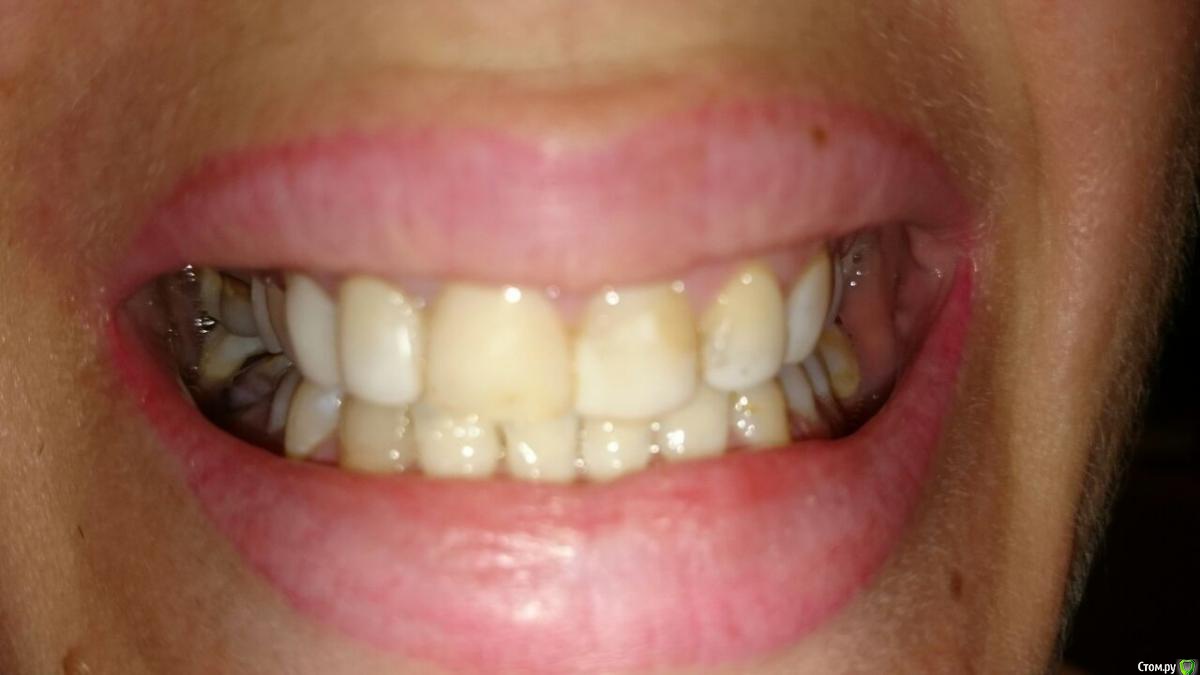

Валерьич Опубликовано 24 сентября, 2016 Поделиться Опубликовано 24 сентября, 2016 Добрый день. Снимок моей супруги ходившей на прием сегодня. Одно мнение хорошо,а много- лучше.Пояснение- передние сверху в винирах, которым 13 лет. Пора менять, это факт. Те что справа коренные под пломбами темные, верхний как бы амортизирует. Врач(или рвач?)- сказал что виниры надо убирать, зубы прятать под коронки. Насчитали 300 тысяч за 6 коронок . В общем мы в шоке от этой суммы, вроде в бюджетную клинику ходила и тут такое.Прошу многоуважаемое сообщество посмотреть снимок и дать план лечения. посоветовать с чего начинать если и вправду о таких суммах идет речь.Жена коронки вперед не хочет однозначно... 2 Ссылка на комментарий

Валерьич Опубликовано 24 сентября, 2016 Автор Поделиться Опубликовано 24 сентября, 2016 Сфоткали как смогли. Ссылка на комментарий

red_butler Опубликовано 25 сентября, 2016 Поделиться Опубликовано 25 сентября, 2016 Врач(или рвач?) к чему клеить ярлыки??? Жена коронки вперед не хочет однозначно... хотеть не хотеть, уже не важно, если не будет коронок на зубах, то будут на коронки на имплантах.По плану... профессиональная гигиена и затем1. удалять зубы мудрости и возможно 4.62. перелечивать 1.63. ревизия корневого канала 2.14. создания места для протезирования в области 3.6 (брекеты)5. имплантация в позицию 3.6 и возможно 4.66. протезирование вкладками и коронками 1.6 2.1, импланта/тов, фронт керамические коронки или виниры. А главное увидели мой вопрос не про лечение а стоимость. я тоже увидел... Насчитали 300 тысяч за 6 коронок . В общем мы в шоке от этой суммы, вроде в бюджетную клинику ходила и тут такое. Прошу многоуважаемое сообщество посмотреть снимок и дать план лечения. посоветовать с чего начинать если и вправду о таких суммах идет речь. 1 1 Ссылка на комментарий

DmitrySH Опубликовано 27 сентября, 2016 Поделиться Опубликовано 27 сентября, 2016 Маленькое уточнение.Тканей у зуба 21 фактически нет, соответственно коронка. Можете ее обозвать полным виниром, можно керамической реставрацией. Ссылка на комментарий